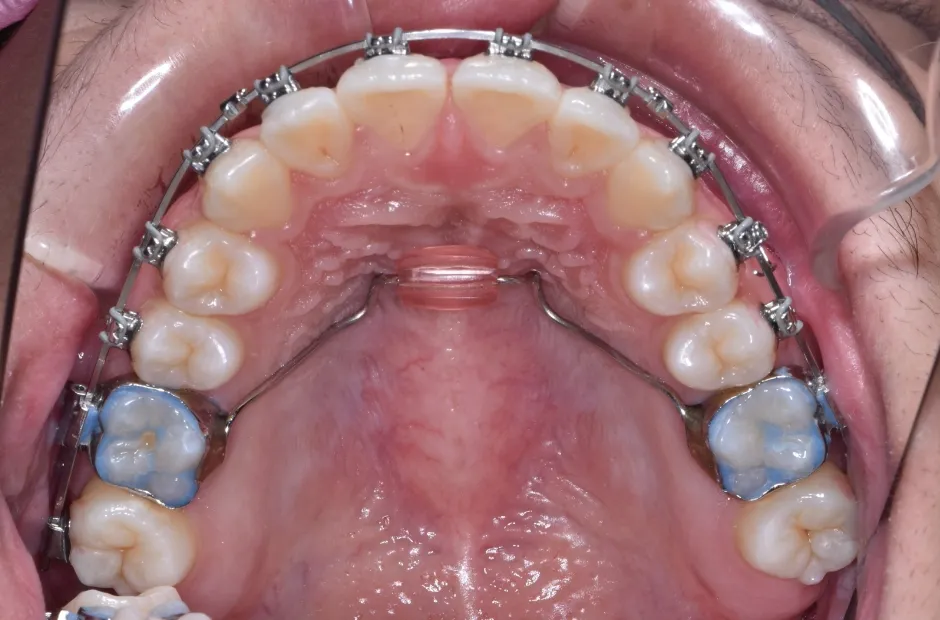

叢生

| 診断名・主訴 | 叢生 |

|---|---|

| 年齢・性別 | 43歳・女性 |

| 治療期間・回数 | 2年7か月 27回 |

| 治療に用いた主な装置 | 舌側矯正 |

| 抜歯部位 | 両顎4,4 |

| 治療費 | 100万円(税抜) |

| リスク・副作用 | 装置による違和感・疼痛・歯肉退縮・歯根吸収・虫歯のリスクなど |

治療中